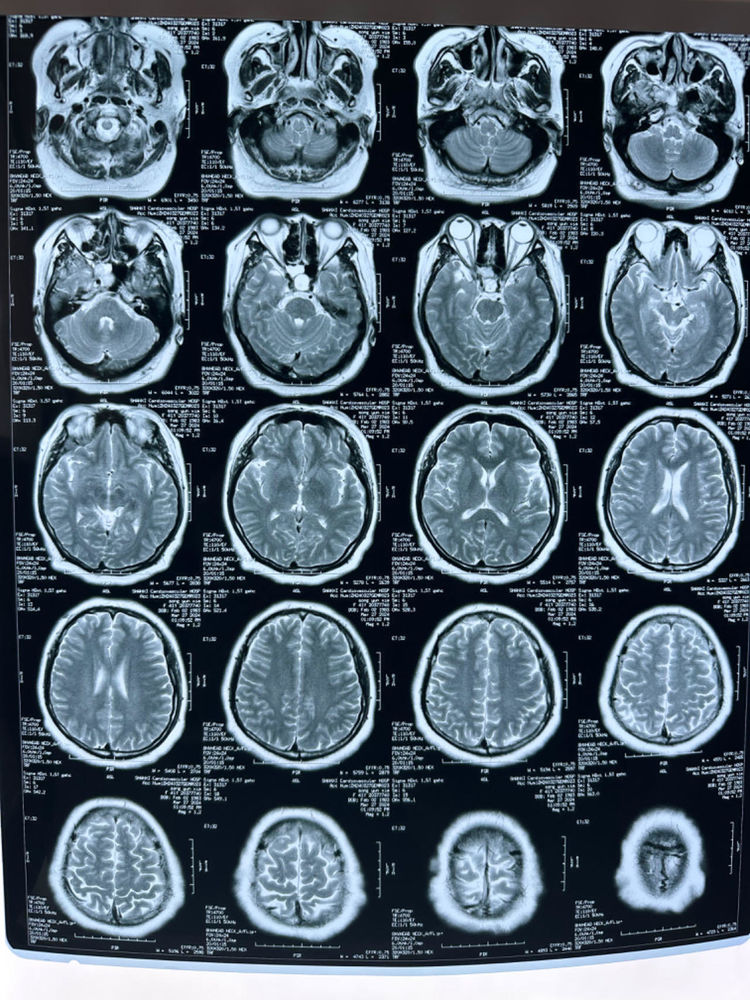

经核磁室、CT室、检验科及神经外科多学科协作讨论后,诊断为:右侧蝶窦外侧隐窝脑脊液鼻漏伴脑膜脑膨出。遂迅速制定详细手术方案,并顺利完成了内镜经鼻右侧蝶窦外侧隐窝脑脊液鼻漏修补术+股外侧筋膜部分切除术。